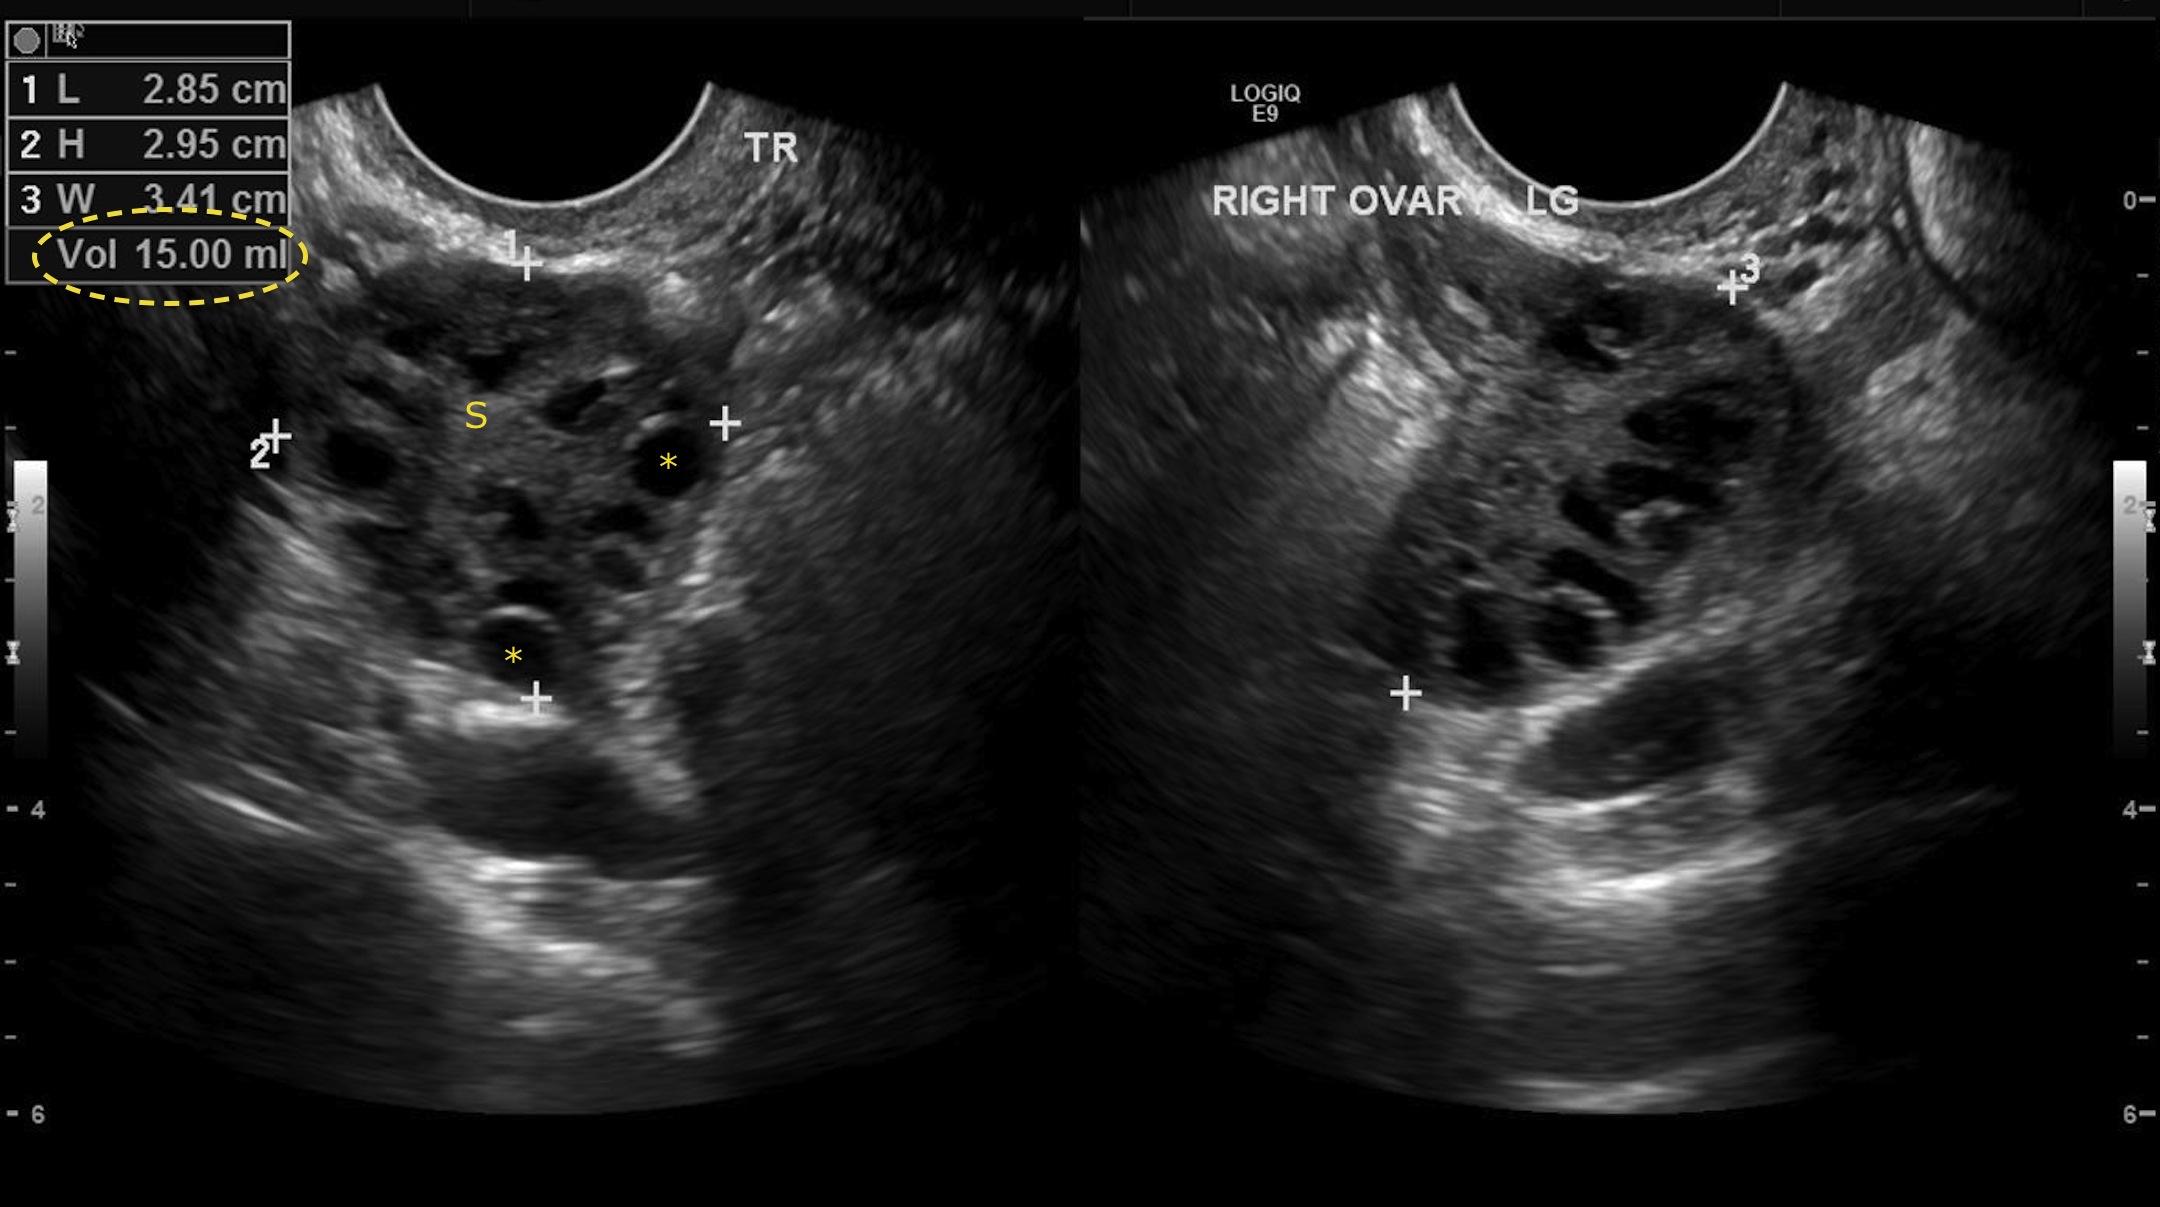

Polycystic Ovary Syndrome and Its Effects on Mental Health in Adults and Adolescents

Halley Eldridge